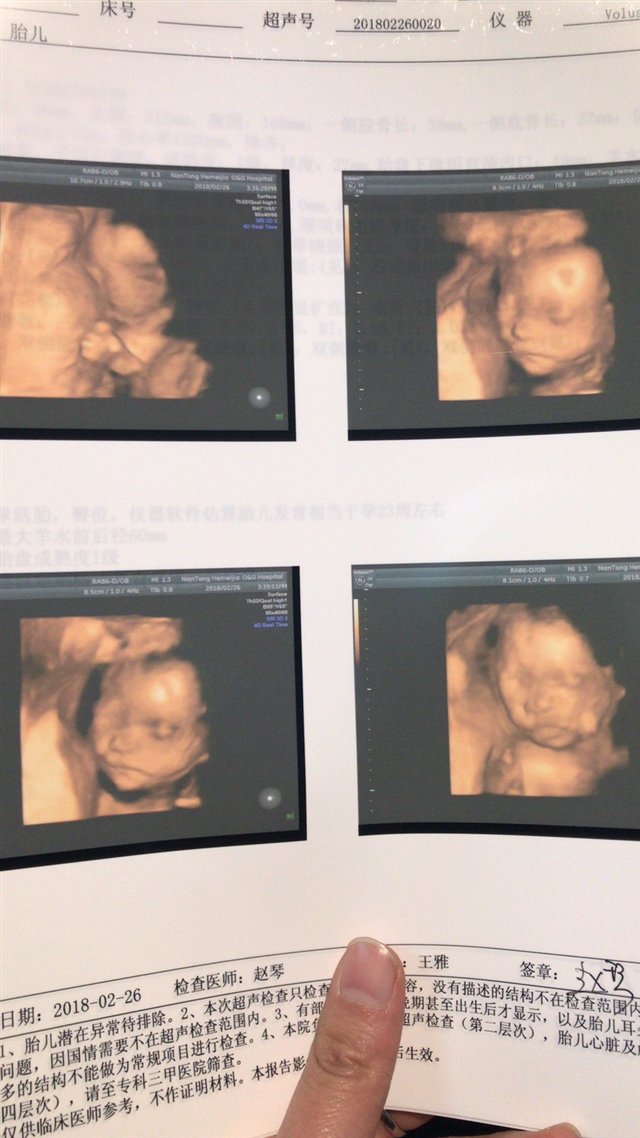

笨笨熊

孕20周+6天